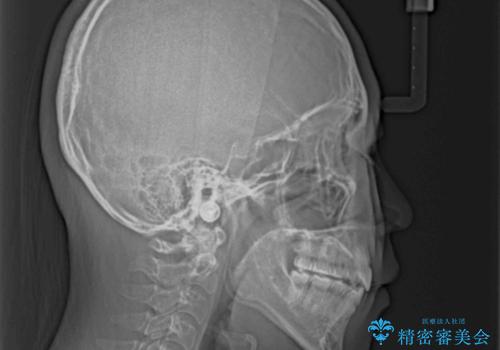

舌の突出癖を改善するためのトレーニングをしっかりと行っていただいたことで、比較的スムーズに治療を進めることができました。

口元の突出感もしっかりと改善することができました。